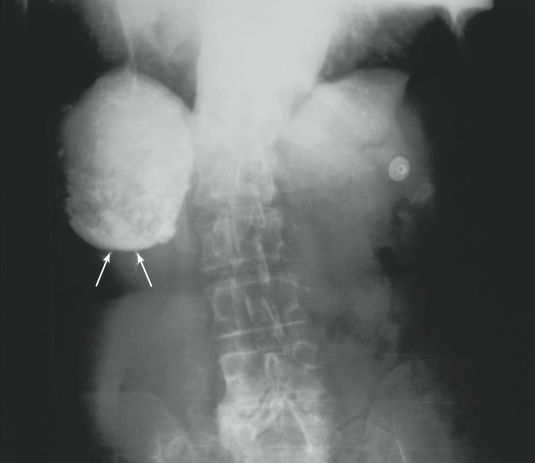

A 79-year-old woman who had a prosthetic mitral valve came to the emergency department (ED) because of severe hypotension; the cause was determined to be an acute upper GI hemorrhage.

During the workup in the ED, a palpable nontender mass was discovered in the right upper quadrant. An anteroposterior flat plate of the chest and abdomen revealed incidental large calcific densities within the liver (arrows) and pelvis. These proved to be hydatid cysts, a parasitic infection rarely seen in the United States, which frequently involves the liver. When the patient was questioned, she gave a history of extensive travel in the Middle East and South America.

Hydatid cysts represent the larval form of Echinococcus granulosus, a small tapeworm found in the intestinal tract of dogs and intermediate hosts (eg, sheep, cattle, and camels). When the ova are ingested by humans, they migrate to the liver or other organs, where they produce a round or oval density. These cysts are composed of a thick outer membrane and a thin inner wall of germinal cells. Over time, fluid fills and distends the cyst, and the resultant growth pattern resembles that of a neoplasm.

These abdominal cysts may be found in the liver or spleen but rarely in the kidney, bladder, ovary, or prostate. They also can occur in the brain, bones, thyroid, and lung, but they rarely calcify within the lung.

Echinococcosis is most commonly discovered by routine x-ray examination. Specific diagnosis is accomplished by histologic examination; do not attempt diagnostic

aspiration because of the potential for anaphylactic reactions to leakage of cystic fluid and hydatid “sand.” Enzyme-linked immunosorbent assay provides the most sensitive and specific serologic diagnosis. Surgery remains the standard treatment for patients with hydatid cysts, although medical therapy with high-dose mebendazole may be considered for those who are not surgical candidates or who have extensive disease.

(Case and photograph courtesy of Drs Philip Munschauer, Leslie Trope, and William Bailey.)